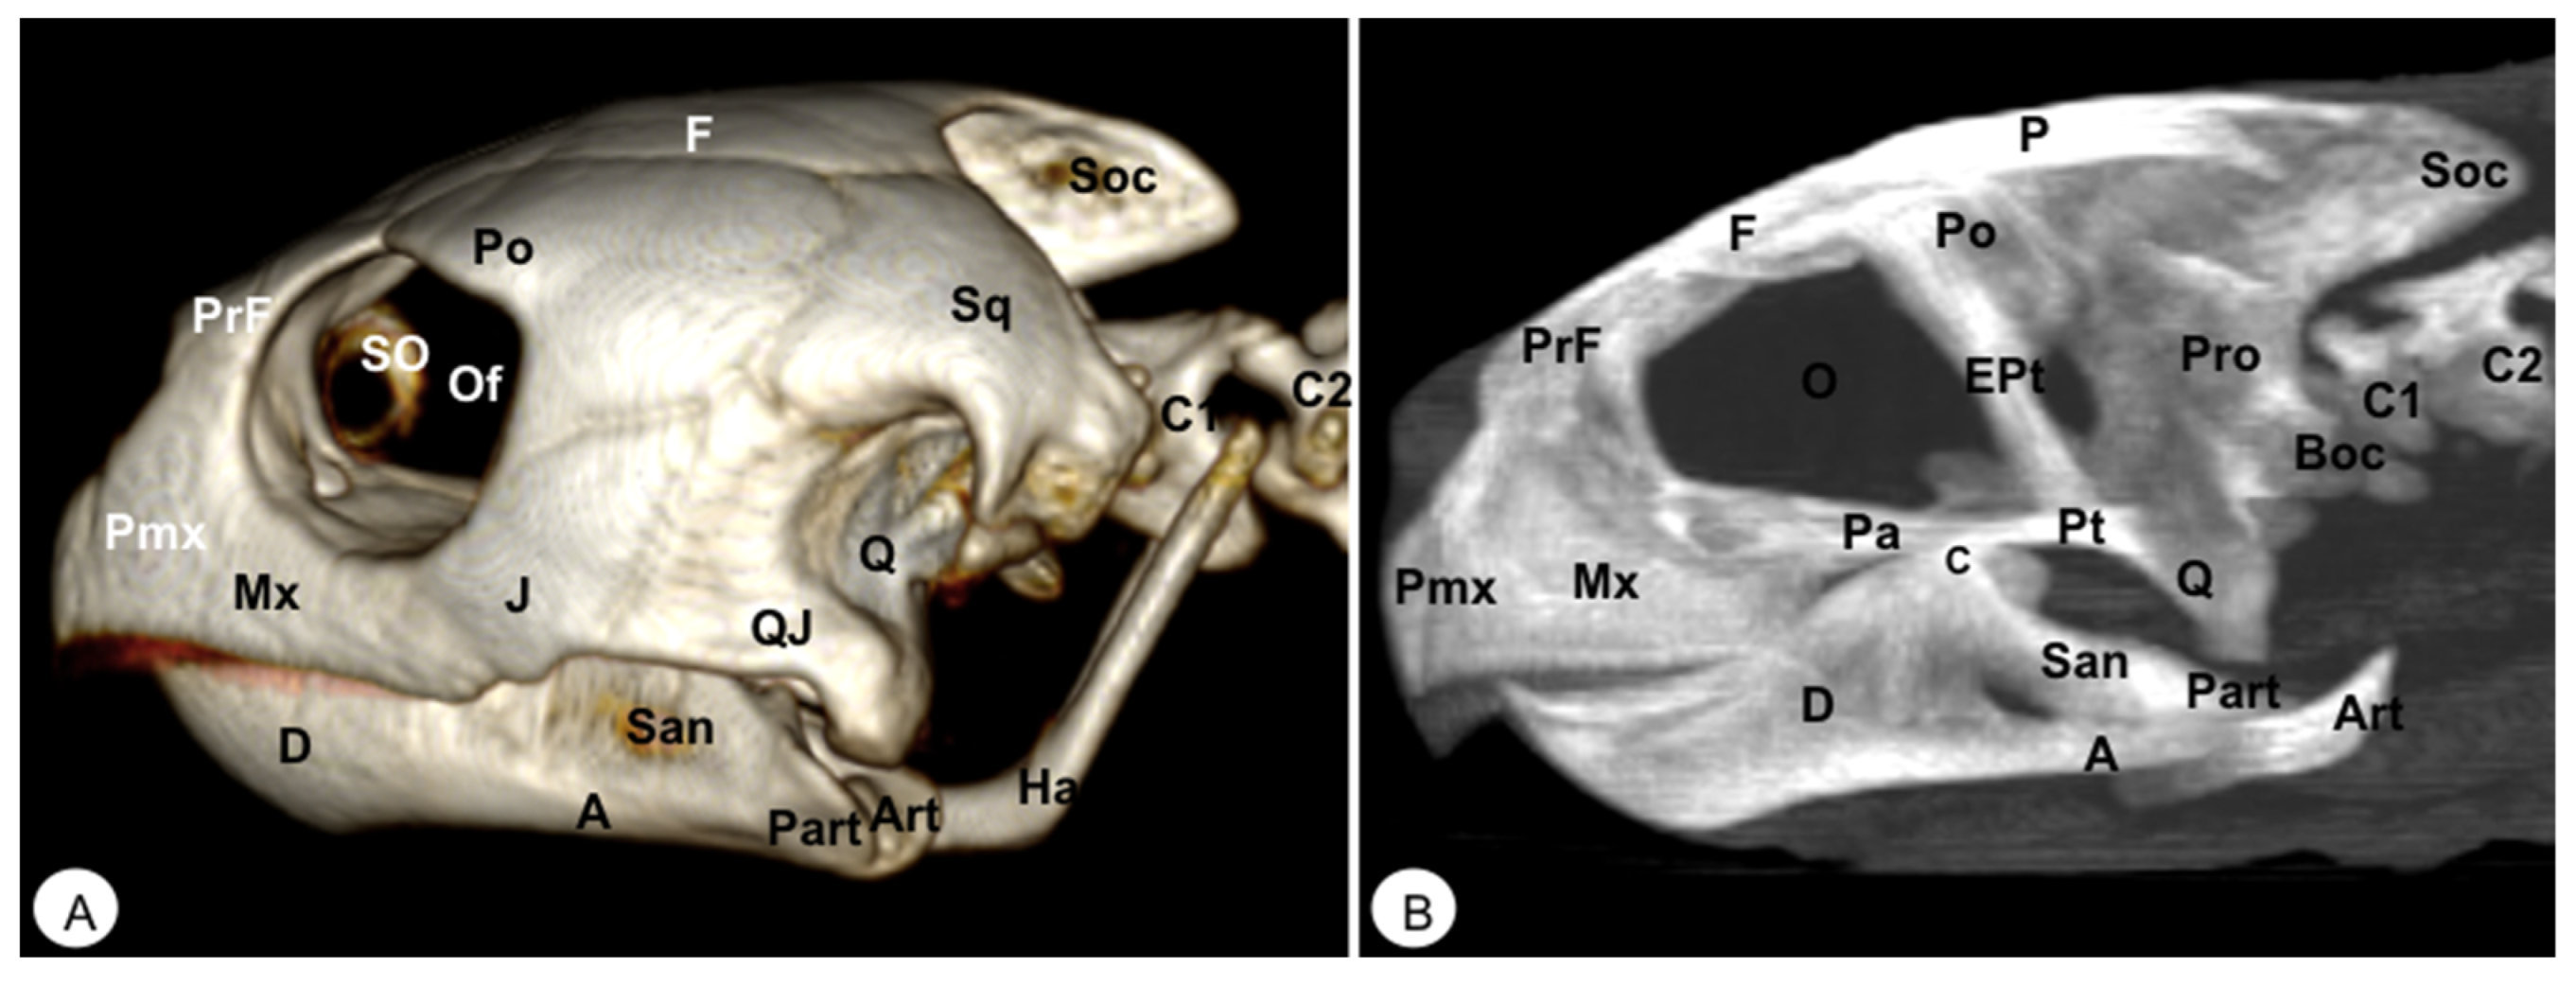

Figure 3. Head of Caretta caretta. (A) Lateral VR image. (B) Medial MIP image. Pmx: Premaxillary bone. Mx: Maxillary bone. PrF. Prefrontal bone. F: Frontal. Po: Postorbital. J: Jugal. SO: Scleral ossifications. QJ: Quadratojugal. Q: Quadrate. Sq: Squamosal. Boc: Basioccipital. Pt: Pterygoid. EPt: Epipterygoid. Pa: Palatine. P: Parietal. Soc: Supraoccipital. Pro: Prootic. C: Coronoid. O: Orbit. Of: Orbital fossa. D: Dentary. A: Angular. San: Surangular. Part: Prearticular. Art: Articular. Ha: Hyoid apparatus. C1: First cervical vertebra. C2: Second cervical vertebra.

The premaxillary bones are narrow, showing a V shape. These bones are the most rostral bony structures of the turtle head (Figure 2A and Figure 3, Figure 4 and Figure 5). Its rostral VR image showed the absence of dorsomedial processes in these bones, allowing the joining of the nostrils (nares) at the midline. This paired bone articulates laterally with the maxillary bone (Figure 2A, Figure 3, Figure 4 and Figure 5A) and caudoventrally with the anterior end of the vomer (Figure 4). We distinguished a similar configuration in the iguana, where it comprises a tooth-bearing alveolar plate. This bone contacts the nasal bone dorsally (Figure 7, Figure 8 and Figure 10), the maxilla caudolaterally (Figure 7, Figure 8 and Figure 10), and the vomer caudomedially (Figure 10B).

3.1.2. MAXILLA (Os Maxillare)

In these species, the frontal bone shows a flat shape and lies in the anterior part of the skull (Figure 2, Figure 3, Figure 5, Figure 7, Figure 8 and Figure 10). The rostral VR turtle reconstruction showed a clear view of the prefrontal and frontal bone junctions (caudomedially). Therefore, the frontal bone contacts the prefrontal bone (rostrally), the postorbital bone (laterally), and the parietal bone (caudally) (Figure 2, Figure 3 and Figure 5). As our animals were adults, we could observe how this bone was excluded from the orbit. The VR and MIP images of the green iguana showed that the prefrontal bone contacts rostromedially with the nasal bone, rostrolaterally with the lacrimal bone (paired small bones located in the lateral region of the orbit observed only in the iguana), and caudomedially with the frontal bone (Figure 7, Figure 8 and Figure 10). The frontal bone is broad and forms a major component of the skull roof, contributing to the dorsal border of the orbit. It meets the prefrontal bone rostrolaterally, the postfrontal bone caudolaterally, and the parietal bone caudally (Figure 7, Figure 8 and Figure 10). Laterally, it is differentiated from the postorbital by the postfrontal bone.

3.1.7. POSTFRONTAL-POSTORBITAL

The postorbital bone forms part of the temporal arch, and most of the posterior margin of the orbit. This bone contacts dorsocaudally with the parietal bone, anterodorsally with the prefrontal bone, and ventrally with the jugal bone (Figure 2, Figure 3 and Figure 5), excluding, therefore, the frontal bone from the orbit. It reaches the squamosal caudally (Figure 3A and Figure 5) and contacts the prefrontal bone rostrally (Figure 2A, Figure 3A and Figure 5). Regarding the iguana, those bones were broad and could be well identified in VR and MIP rostral, dorsal, and lateral images as two different bones. The postfrontal bone arises in the caudodorsal part of the orbit and meets the frontal bone (rostromedially), the parietal bone (caudomedially), and the postorbital bone (caudolaterally) (Figure 7, Figure 8 and Figure 10). In contrast, the postorbital bone meets the postfrontal bone dorsally, the squamosal bone caudolaterally, and the jugal bone rostrolaterally (Figure 8 and Figure 10).

3.1.8. PARIETAL (Os Parietale)

3.1.9. JUGAL (Os Jugale)

The jugal bone is one of the main elements of the zygomatic arch under the orbit in both species, showing an “L” shaped configuration in VR and MIP lateral images. Rostral and lateral VR images were quite useful in distinguishing the arrangement of this bone at the caudoventral border of the orbit. Moreover, the rostral, lateral, and ventral VR and MIP images of the turtle show how this bone contacts dorsocaudally with the postorbital bone, rostrally with the maxilla, and posteriorly with the quadratojugal bone (resulting in the zygomatic arch). In contrast, the jugal bone in the iguana is observed as a curved bone (seen by rostral, lateral, and dorsal VR and MIP images) that runs forward along the orbital border to make contact with the lacrimal (dorsally) and maxillary bones rostrally. Caudodorsally, it angles slightly upwards to meet with the postorbital and the squamosal bones. Ventrally, it contacts the ectopterygoid bone.

3.1.10. QUADRATE (Os Quadratum)

3.1.11. QUADRATOJUGAL (Os Quadratojugale)

The quadratojugal bone was only observed in the turtle’s head and forms part of the anteroventral border of the cavum tympani and half of the cheek emargination. They are well seen in the lateral VR image. This roughly square bone joins the jugal anteriorly, the postorbital anterodorsally, the squamosal caudodorsally, and the quadrate bone caudally (Figure 3A).

3.1.12. SQUAMOSAL (Os Squamosum)

3.1.13. PTERYGOID (Os Pterygoideum)

3.1.14. EPIPTERYGOID

The basioccipital bone in the turtle is a rectangular-shaped bone located in the posterior half of the planum basale, contacting the basisphenoid (rostrally) and exoccipital (caudally) bones, forming part of the floor of the cavum cranii (Figure 3B, Figure 4 and Figure 6). In the iguana, it roughly reaches the parabasisphenoid and caudally the occipital bone (Figure 11), forming part of the occipital condyle.

The supraoccipital bone is an unpaired midline element located in the posterodorsal portion of the skull (Figure 3, Figure 4, Figure 5, Figure 6, Figure 10 and Figure 11). Both turtles and iguanas have a similar configuration. This bone has a broad contact with the posteromedial margins of the parietals (Figure 3B, Figure 5A, Figure 10 and Figure 11). Posteroventrally, it contacts the opisthotic and otoocipital, forming part of the medial part of the occipital condyle, near the foramen magnum (Figure 6 and Figure 11). These features were observed by VR and MIP reconstructions in the caudal view of both species.

3.3.1. DENTARY (Os Dentale)

The dentary bone is the major bone of the mandible in both species. Its lateral surface appears pierced by small foramina, where mandibular nerve branches and blood vessels run. In the iguana, it carries pleurodont teeth. This bone was better visualized in the rostral, lateral, and ventral VR and MIP images. Either in the turtle or the iguana, it joins the coronoid and the surangular caudodorsally (Figure 2, Figure 3, Figure 4, Figure 8 and Figure 9), the angular caudoventrally (Figure 3, Figure 4, Figure 8 and Figure 9), and the splenial bone medially.

3.3.2. ANGULAR (Os Angulare)

The angular bone is a laminar bone located in the caudal aspect of the mandible from the rostromedial to the caudolateral aspect, forming the ventrocaudal margin of the mandible. This bone was well visualized in the lateral MIP and VR images of these species (Figure 3 and Figure 8). The connections of the angular bone in both species are the dentary bone rostrally, the splenial and prearticular bones dorsomedially, and the articular bone in the caudal direction.

3.3.3. SURANGULAR (Os Surangulare)

The surangular is a widely flat bone located below the coronoid along the dorsal border of the mandible and forming most of the caudolateral surface of the mandible. In both species, it is located posteriorly and slightly dorsal to the dentary, connected to the coronoid rostrodorsally, to the angular bone caudoventrally, and to the articular bone medially (Figure 3 and Figure 8).

3.3.4. CORONOID (Os Coronoideum)

The coronoid is a broadly triangular bony structure located approximately medial to each branch on the caudodorsal aspect of the mandible. This process is the highest part of the mandible in both species. This bone was better visualized in the lateral MIP view of the iguana than in the turtle, where we could distinguish how the coronoid tends to be slightly higher and more dorsally pointed than in the loggerhead turtle. Both species have the same configuration where the coronoid meets the dentary rostrolaterally, the surangular caudolaterally, the articular caudoventromedially, and the splenial bone ventromedially (Figure 3B, Figure 7 and Figure 8).

3.3.5. PREARTICULAR (Os Prearticulare)

The prearticular bone is a wide, flat lamella overlying a large area of the caudomedial surface of the lower jaw, forming a long, narrow process whose dorsal border constitutes the medial border of the adductor fossa. This bone reaches the coronoid rostrodorsally, the articular bone caudomedially, and the angular ventrally (Figure 3). If the splenial bone is present, this bone is sutured to the rostral edge of the prearticular bone.

3.3.6. ARTICULAR (Os Articulare)

The articular bone is an irregularly block-shaped bone found at the caudal edge of the mandible in the turtle and the iguana. It was observed using both VR and MIP techniques (Figure 3, Figure 6, Figure 7, Figure 8, Figure 9, Figure 10 and Figure 11) and had the same configuration in both species. Thus, it joins with the surangular laterally and the angular ventrally, forming the retroarticular process, and dorsally with the coronoid bone.

3.3.7. HYOID APPARATUS (Os Hyoideum)

The hyoid apparatus is located in the intermandibular space. It provides support to the tongue, pharynx, as well as floor of the mouth. This apparatus consists of a pentagonal piece, which has three structures: a central (basihyal) structure, an anterior process, and two caudolateral processes (Figure 3A, Figure 4, Figure 5, Figure 6A, Figure 8, Figure 9, Figure 10A and Figure 11).